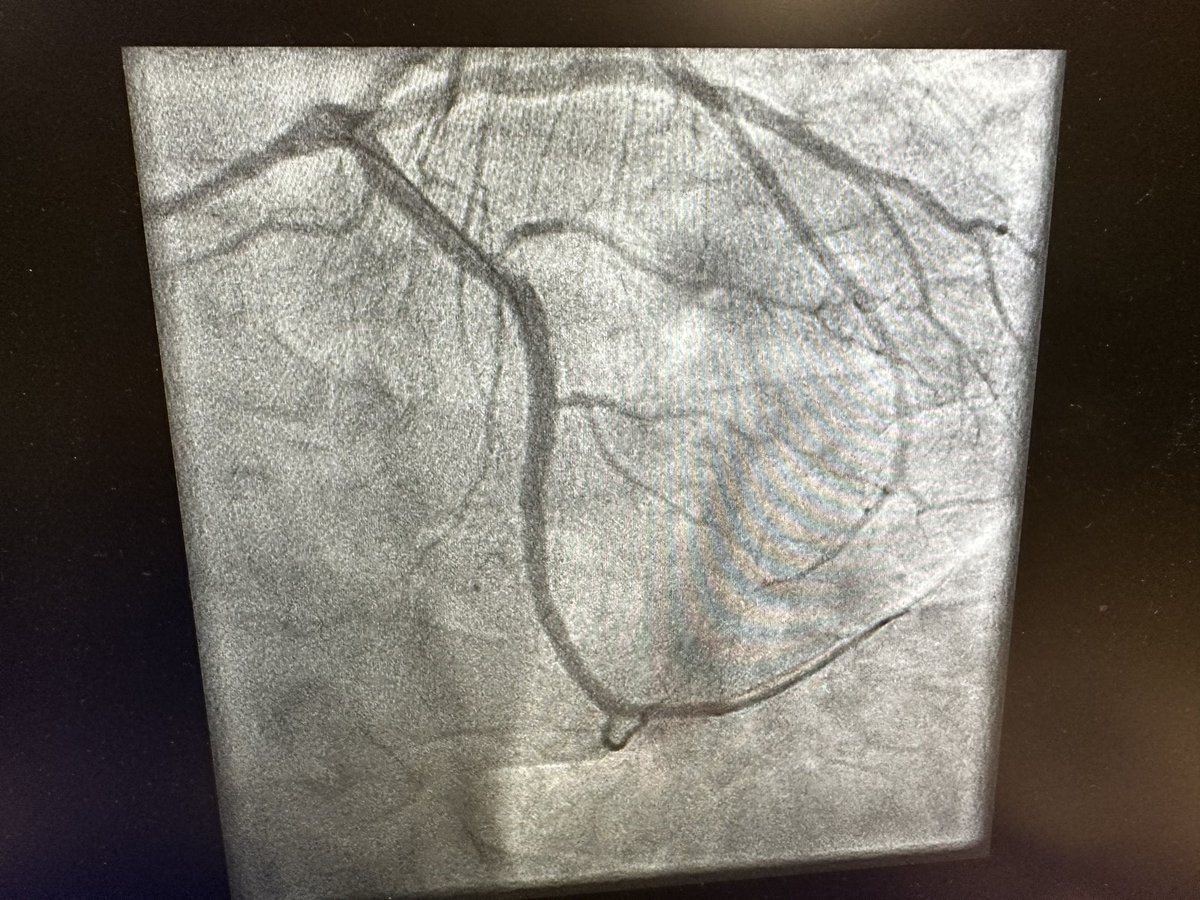

NHS failing- 2x ppci overnight. This pt phoned ambulance at 10 pm. Phoned further 21x with worsening CP. at 6am wife chose to drive him in- VF - ivus guided PPCI. 2nd pt- waited 4 hrs for ambulance, wife drove him in. This is not how to run a service Dr Asif Qasim MA PhD FRCP Dr Shrilla Banerjee MD FRCP 💙